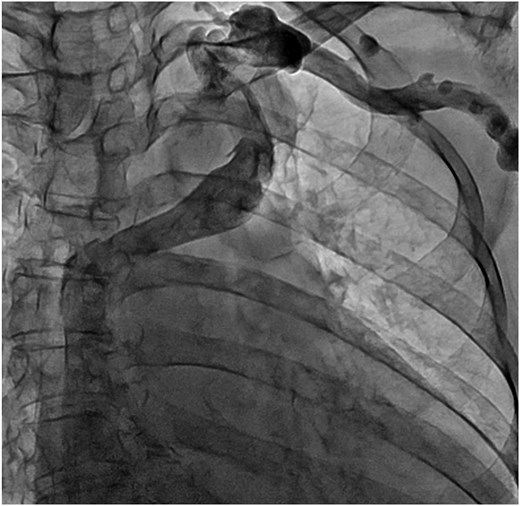

Venography of the left upper limb. The ALBCV joined the SVC, and no communication was observed between the ALBCV and coronary sinus.

A 78-year-old woman with severe mitral regurgitation (MR), tricuspid regurgitation, and atrial fibrillation was admitted with worsening heart failure. She had hypertension, but no known CHD. She was 138 cm tall, weighing 34.6 kg, with a body mass index of 18.3 kg/m2. Her vital signs were normal. The N-terminal fragment of pro B-type natriuretic peptide was elevated at 2577 pg/mL. Chest radiography revealed cardiac enlargement and bilateral pulmonary edema. Transesophageal echocardiography (TEE) revealed shortening of the anterior and posterior leaflets of the mitral valve, with thickening of the commissure, indicating severe MR (Fig. 1 and Video 1). The tricuspid annulus diameter increased to 29.4 mm. No congenital heart diseases were detected. Contrast-enhanced computed tomography (CT) revealed that the left innominate vein coursed posterior to the ascending aorta, the so-called ALBCV, and joined the superior vena cava (SVC) 3 cm from the right atrium (Fig. 2 and Video 2). Venography of the left upper limb confirmed the ALBCV (Fig. 3 and Video 3). No communication existed between the ALBCV and the coronary sinus.